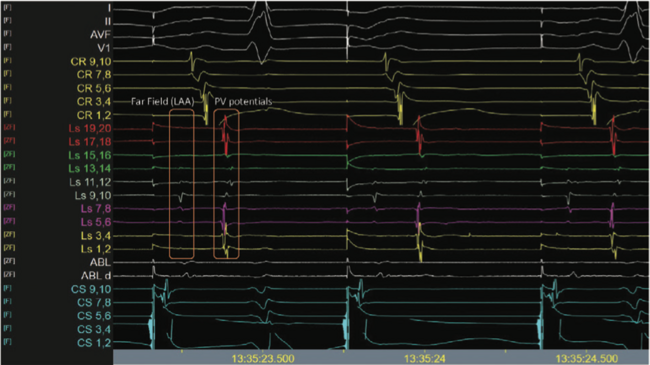

The main takeaway was that the study validated the clinical relevance and quality of the PURE EP™ signals over conventional signal sources. There was a 93% consensus in responses from the blinded EP reviewers. They deemed signals from the PURE EP™ System as having a cumulative 75% superiority in signal quality and physician confidence. There was an 83% improved confidence in interpreting near-field versus far-field signal components, and a 73% improvement in visualization of small, fractionated signals of clinical importance.

The study results show that PURE EP™ provides the most accurate physiologic signal information available for use during our ablation procedures. We get higher fidelity visualization of the intracardiac signals without issues associated with signal saturation and noise, which is so common in the EP lab. In addition, with PURE EP™, we don’t see the usual problematic artifact such as ringing, which is caused by over-filtering in conventional systems and can be misleading.

I’m very excited that we finally have what I consider to be a major technological enhancement in one of the most important areas of interventional cardiac electrophysiology. High-quality signal acquisition is central to any ablation procedure, and absolutely mission critical for many of our cases. Over the past several years, other technological advances such as improved mapping systems, force-sensing ablation catheters, and intracardiac echo, have allowed us to successfully tackle more challenging arrhythmia substrates. But as we’ve discussed, the most complex arrhythmias often have important small, high-frequency, low-amplitude potentials that are difficult to discern with current mapping and recording systems. Those signals, when they’re tagged and incorporated into the 3D electroanatomical map, help us better understand the circuit or arrhythmia focus, and identify areas that require ablation therapy.